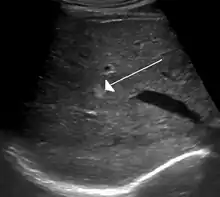

On ultrasound, cavernous haemangiomas in liver appeared as homogenous, hyperechoic lesions with posterior acoustic enhancement. On CT or MRI scans, it shows peripheral globular/nodular enhancement in the arterial phase, with portions of attenuation of enhancing areas. In the portal venous phase, it shows progressive centripetal enhancement. In delayed phase, it shows retention of contrast. It shows a high signal on T2 weighted images.[23]